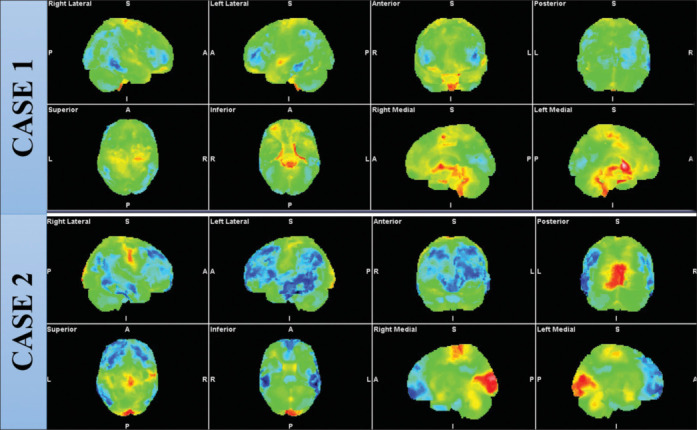

Obsessive-compulsive disorder is among the most extensively researched mental health disorder. Various metabolic neuroimaging research findings are consistent but still nonconclusive. The major limitation is a homogeneous sample. There are research findings which have established the impact of treatment in changing brain metabolism. Therefore, it is important to highlight differential metabolic changes with respect to treatment staging and its outcome. It will also help to individualized neuromodulation protocol based on differential metabolic findings. This study highlights the distinct differential fluorodeoxyglucose metabolic changes among two distinct cases: drug-naïve and treatment-refractory.